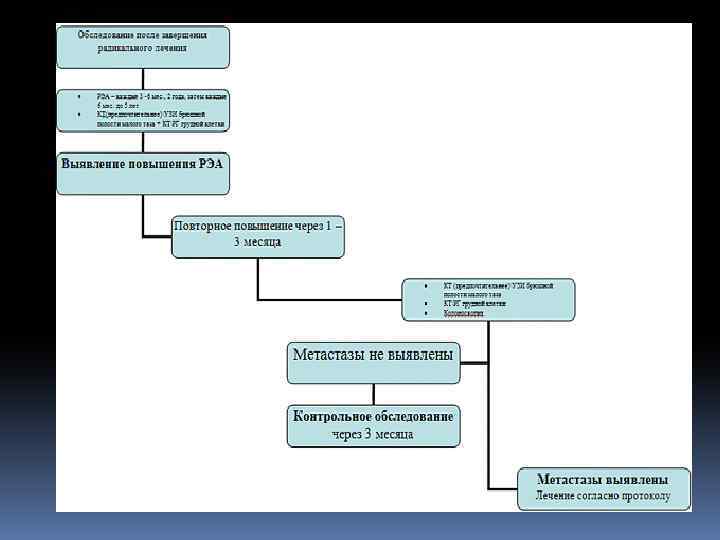

В группе больных повышенного риска развития колоректального рака необходимо проведение скрининговых исследований. Используют тест на скрытую в кале кровь, определение карциноэмбрионального антигена, про водят генетическое тестирование, выполняют колоноскопию. Осложнения. Наиболее частыми осложнениями являются непрохо димость кишечника, воспаление в окружающих опухоль тканях и перфора ция опухоли, кишечные кровотечения, свищи между ободочной кишкой и соседними органами.